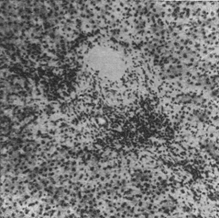

Е

Рис. 2. Болезнь Боткина (девочка 4 года). Персистирование инфильтратов в портальном тракте после клинического выздоровления.

ще некоторое время после клинического выздоровления о незаконченности процессов восстановления свидетельствуют: лимфогистиоцитарные инфильтраты в портальной зоне (рис. 2), полиморфизм печеночных клеток, обилие многоядерных печеночных клеток, наличие липофусцина, а иногда и железосодержащего пигмента в ретикулярных клетках и наличие желчных тромбов в отдельных желчных капиллярах. Спустя более или менее длительный период (3—4 мес.) после перенесенной Б. б., наступает либо полное морфологическое восстановление, либо обнаруживаются остаточные изменения, выражающиеся в очаговом, портальном или центральном фиброзе; последний, как показывают исследования сериальных пункционных биопсий печени, с течением времени иногда полностыо исчезает. Интенсивность описанных воспалительных, некротических и регенеративных процессов может значительно варьировать: в некоторых случаях легкого течения II фаза полностью выпадает, и I фаза непосредственно переходит в III. Морфологические изменения печени при желтушной и безжелтушной формах Б. б. при инфекционном гепатите (спонтанном) и при сывороточном (шприцевом) одинаковы. Морфологические изменения печени при рецидивах Б. б. и повторных заболеваниях аналогичны изменениям при острой форме.Одним из возможных вариантов течения Б. б. является перихолангиолитическпй или холестатический гепатит, при котором клинически на первый план выступают признаки механической желтухи (более или менее выраженные и при обычном течении болезни) при отсутствии препятствий во внепеченочных желчных ходах. При микроскопическом исследовании находят: